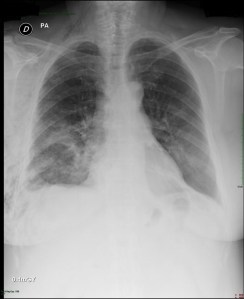

The current treatment algorithm, which often starts as several weeks of outpatient antibiotics, (usually initiated for treatment of community acquired pneumonia that develops into a parapneumonic effusion), that engenders an even longer period after subsequent follow up chest x-rays, then CT scan fail to show improvement.

A pneumonia in late September, becomes an effusion in October, then progresses to empyema as various strategies are attempted and fail.  One antibiotic is switched to another, a pigtail is placed in radiology (with partial results), then perhaps, a larger tube, and fibrinolytics.  Then, only then – is the thoracic surgery service consulted.

At this point, the patient has been sick for several days to weeks.   As they remain sick, there is a decline in both nutritional and functional status.  The “spry” and youthful 75-year-old becomes a mostly bedridden and frail elderly patient.  This too, works against the patient and their recovery, as internal medicine physicians and pulmonologists are reluctant to refer this now frail patient due to the perceived rigors of surgery.  This fear of thoracotomies dwarfs the very real risks of prolonged illness and debility.